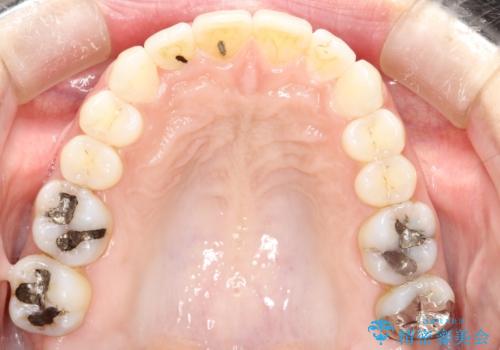

- 前歯のがたつきを気にされて来院されました。

右上の前から2番目の歯が前方に大きく傾いており、下の前歯もガタガタしていました。

インビザラインにて、歯と歯のあいだをわずかに削り並べる計画としました。

しっかりとマウスピースを使用していただけたので、順調に治療を終えることができました